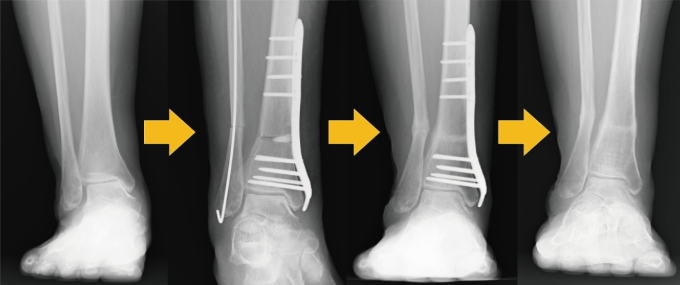

治療の基本は鎮痛剤・湿布などの薬物療法、またサポーターや足底板などの装具療法になります。保存的治療で改善しない場合は手術療法を選択します。手術療法としては軽症例では関節鏡というカメラで関節の中をお掃除するような負担の少ない手術から、変形が進行すると関節固定や人工関節置換術といった手術が行われます。その中である程度変形しているものの程度が部分的な場合(多くの場合は内側)は「下位脛骨骨切り術」が実施されます。この骨切り術はすねの骨の足首に近い方を切って並びを矯正し足首の負担を軽くする方法です(図参照)。アライメントが改善されると痛みが軽減します。